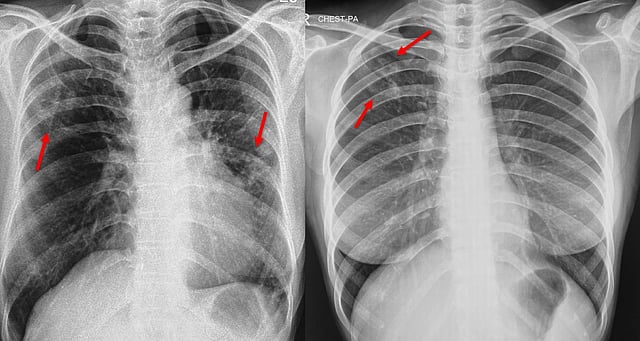

Chest X-Rays Fall Short In Detecting Silent Tuberculosis Cases, Says Study

Chest X-rays miss nearly half of asymptomatic TB cases, a study finds. Standard screening may vastly underestimate TB in high-burden nations, urging universal sputum tests for accurate detection.

Despite being a cornerstone of tuberculosis (TB) detection for decades, chest X-rays may be missing a significant share of infections — particularly among individuals who show no symptoms — a new study published in The Lancet Global Health has revealed.

The research, led by scientists from the University of Cape Town, South Africa, found that nearly half of asymptomatic TB cases among household contacts of infected individuals were missed by standard chest radiographs. The findings raise questions over the adequacy of current screening tools used in high-burden countries, including India.

Pulmonary tuberculosis was confirmed in 5.2 per cent of the participants, of whom a striking 82.4 per cent reported no symptoms. Moreover, chest radiographs failed to detect 40 per cent of these confirmed infections.

The sensitivity of chest radiographs for detecting asymptomatic tuberculosis stood at 56.1 per cent, while combining symptom-based and X-ray screening raised overall sensitivity to just 64 per cent — well below the WHO’s target of 90 per cent sensitivity and 70 per cent specificity for an effective screening test.